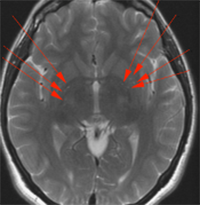

그림 1. 뇌 백색질의 광범위 허혈 병변. 코로나19 환자의 MRI diffusion에서 (인체 내 물 분자의 움직임에 기반) 뇌 반구 백색질 내(A, 흰색 화살표), 뇌량(B, 적색 화살표), 대뇌핵, 중소뇌각, 소뇌 반구 내(B, 흰색 화살표)2다수의 허혈 병변을 볼 수 있다.

그림 2. 뇌 백색질의 광범위 허혈 병변. 종사 질병 환자의 MRI에서 뇌 반구 백색질 내, 대뇌핵(적색 화살표) 내 다수의 허혈 병변을 볼 수 있다. 이는 수술 후 사라졌다.